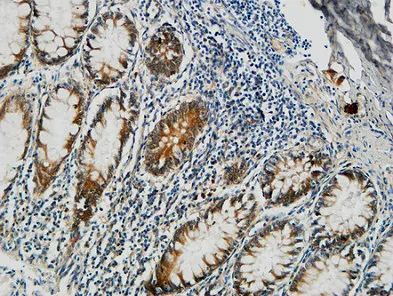

Somatostatin Rabbit Polyclonal Antibody

Cat: APRab18109

Size1:50μl Price1:$118

Size2:100μl Price2:$220

Size3:500μl Price3:$980